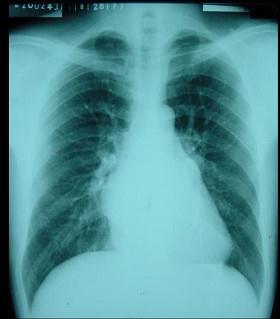

问题 男性,30岁。活动时心慌、气促两年,加重一年,一年前出现“脑栓塞”,心律98次/分,心律绝对不齐,心尖可闻及中重度舒张期隆隆样杂音,胸骨左缘3、4肋间可闻及Ⅱ~Ⅲ/6级收缩期杂音。 心脏正位片如图所示,可以观察到以下哪个描述 ( )

选项 A、肺缺血+主动脉瓣型心 B、左向右分流先天性心脏病 C、肺淤血+主动脉瓣型心 D、肺缺血+二尖瓣型心 E、肺淤血+二尖瓣型心

答案 E